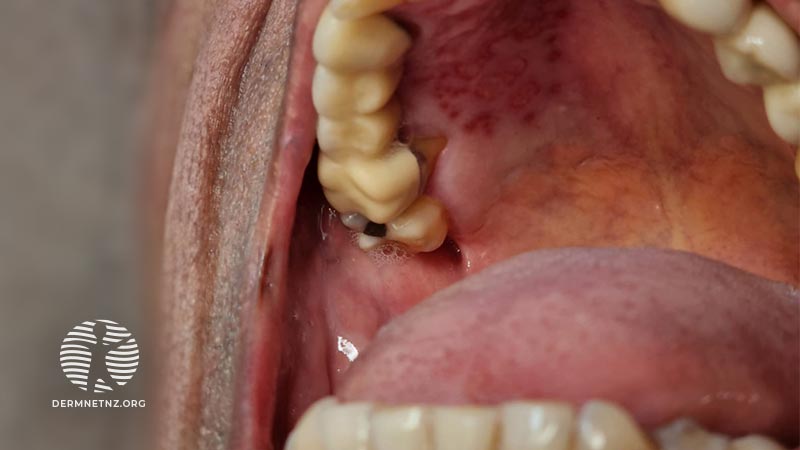

Placeholder image

A cluster of oral ulcers

Read moreArrow right small right